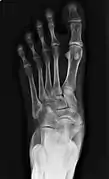

To diagnose accessory navicular syndrome, the foot and ankle surgeon will ask about symptoms and examine the foot, looking for skin irritation or swelling. The doctor may press on the bony prominence to assess the area for discomfort. Foot structure, muscle strength, joint motion and the way the patient walks may also be evaluated. X-rays are usually ordered to confirm the diagnosis. If there is ongoing pain or inflammation, an MRI or other advanced imaging tests may be used to further evaluate the condition.[5]

Radiological images